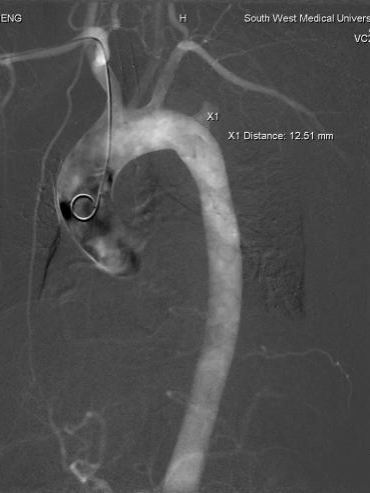

主动脉“修复”介入诊疗技术:

手术中过程图: